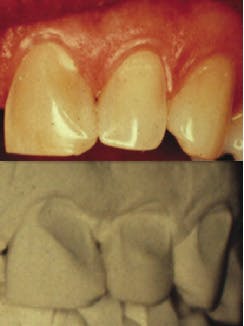

The objective of this paper is to stress the significance of making and retaining conventional diagnostic stone casts of a patient's mandible, maxilla, teeth, and the surrounding tissues. Full-arch diagnostic casts are valuable tools in determining various physiological and morphological changes that take place during the life span of the jaws, teeth, and periodontal tissues (Figs. 1-5).

Digital imaging impressions can also be used to make extremely accurate stone casts, which reproduce the jaws, teeth, gingival tissues, and palatal area (Fig. 6).1-4 Though the intraoral digital scanners are moving rapidly into the profession, use of conventional materials remain the most common source for making impressions. Stone casts are familiar to practitioners and, at this time, provide precise information on the bone, tissues surrounding the teeth, as well as their morphology and position. Use of stone casts can be an effective means of patient education, as they provide comparable observation of the changes that have taken place over time in the position and anatomy of teeth, bone, and soft tissues. A few noteworthy examples are demonstrated in Figs. 1-5.

Occlusion constantly changes, and comparison of the changes on stone casts provide valuable information to the practitioner and can be used to educate the patient.5